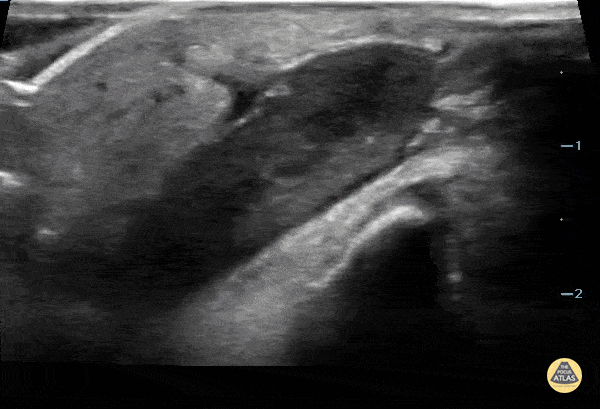

12 yo male with a splinter to the leg that was partially removed. He presented to the ED with redness and swelling of the site. POCUS shows retained FB (wood) with surrounding infection. Contributor: Paul Khalil, MD Nicklaus Children's Hospital @khalil3paul